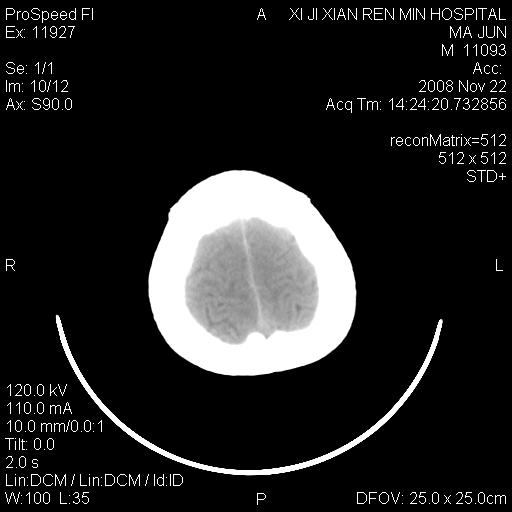

双侧侧脑室前角,三角区旁及半卵圆中心区白质呈低密度改变,半卵圆中心区病灶呈片状融合趋势,无软化征像,脑室无扩张,各神经核团无异常改变,脑皮质无萎缩等征像,结合病史考虑髓鞘发育不良性脑白质病,异染性脑白质营养不良可能性大.不除外多发性硬化等其他改变,建议磁共振检查

脑白质减少,双侧侧脑室额角旁及半卵圆中心可见对称性略低密度影,边缘尚清,考虑脑白质发育不良